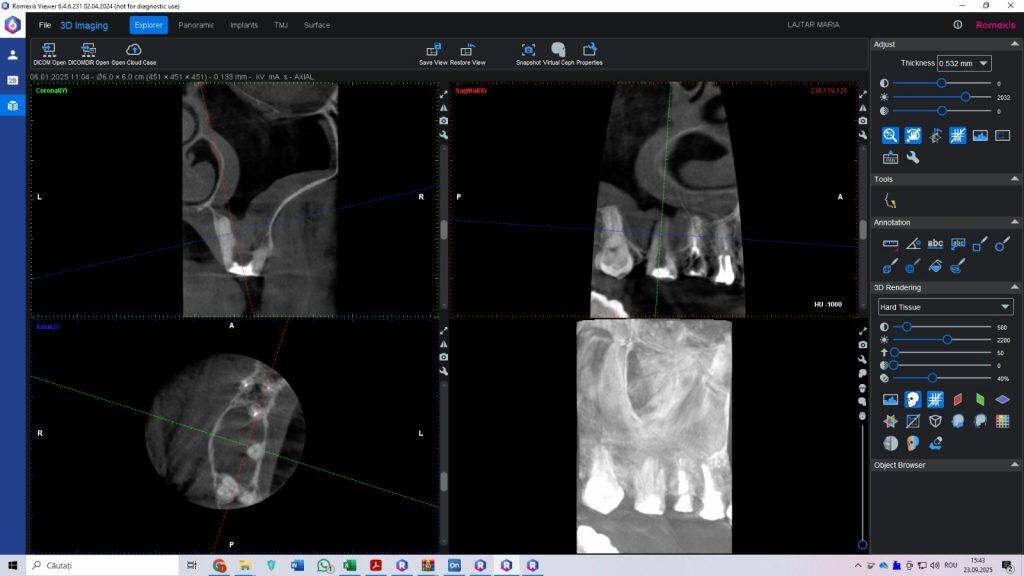

Caz 4 – Molar superior cu rădăcini în sinusul maxilar

Un molar superior cu rădăcini în sinusul maxilar a fost perforat accidental de catre alt medic în timpul primei intervenții (fără microscop), creând o comunicare directă cu sinusul. În endodonția convențională, acest caz ar fi fost considerat netratabil, întrucât lucrul cu hipoclorit de sodiu în sinus este imposibil. Alternativa clasică ar fi fost extracția, sinus lift-ul și implantul – o procedură complexă și de durată.

In clinica noastra, laserul a permis salvarea dintelui, deoarece s-a lucrat doar cu apă și lumină, fără substanțe iritante pentru sinus. Perforația a fost închisă cu un ciment biocompatibil și bactericid, iar dintele a fost restaurat protetic. La CT-ul de control la 9 luni, sinusul maxilar apare complet curat și vindecat.